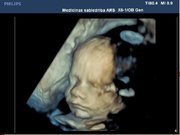

3. Grūtniecības laikā ultrasonogrāfijas pārbaudi nepieciešams iziet 3 reizes:

1. 11 – 13+6. grūtniecības nedēļā (I trimestris)

2. 20 – 22+6. grūtniecības nedēļā (II trimestris)

3. 34 – 35+6. grūtniecības nedēļā (III trimestris) – riska grupa